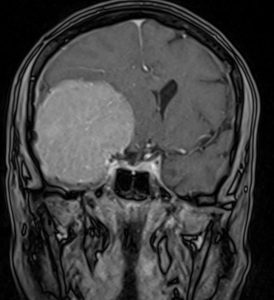

Ασθενής 69ετών με συμπτώματα βραδυψυχισμού και έκπτωση γνωσιακών λειτουργιών.

Ο απεικονιστικός έλεγχος με μαγνητική τομογραφία ανέδειξε ευμεγέθη εξεργασία δεξιά, συμβατή με μηνιγγίωμα πτέρυγας σφηνοειδούς οστού.

Πρόκειται για ένα μεγάλο μηνιγγίωμα το οποίο εμπλέκει πολύ σημαντικά ανατομικά στοιχεία όπως την καρωτίδα και τους κλάδους της και το δεξί οπτικό νεύρο.